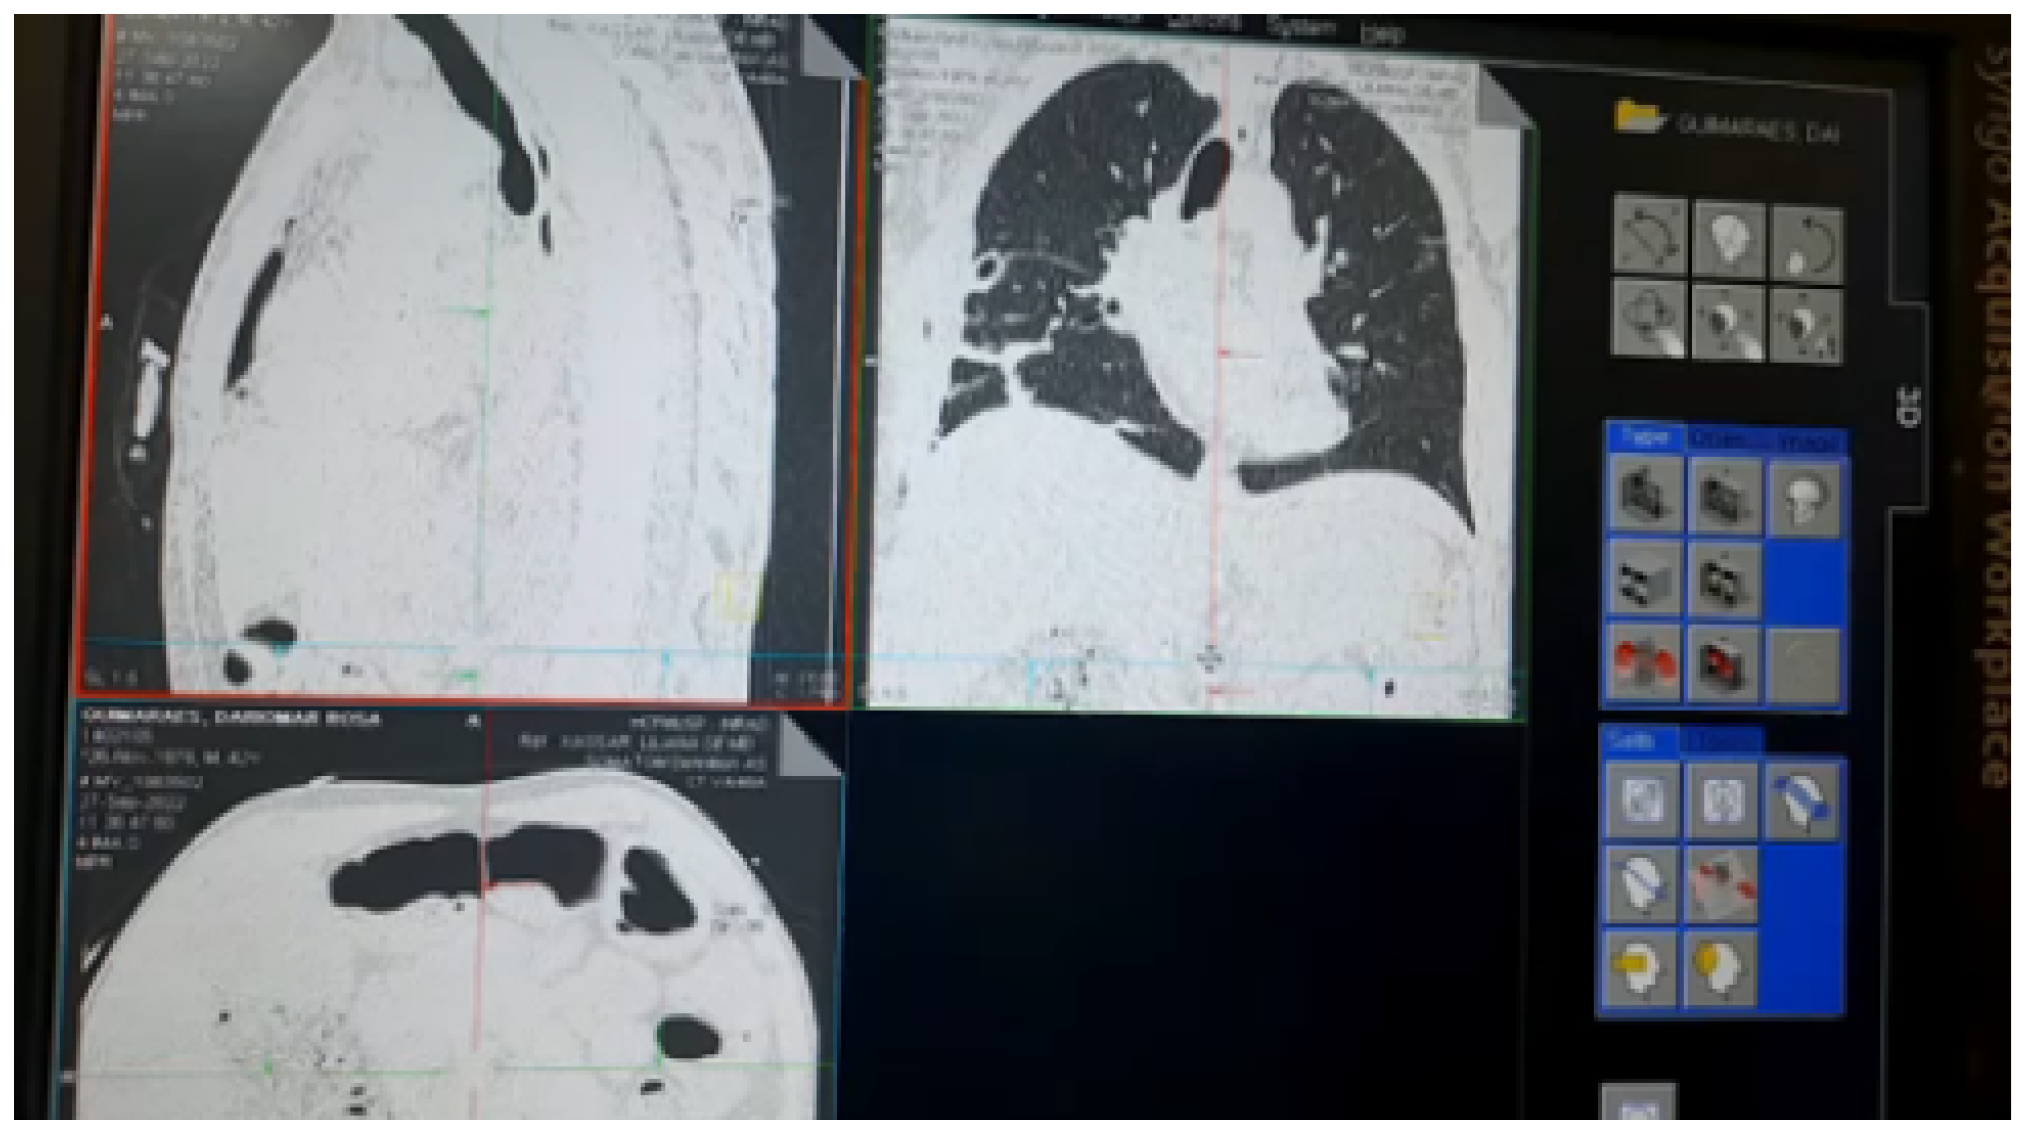

- The second phase is related to PoC-2 involving the same 5G private network remotely connected to the Computational Tomography MRI/CT.

4.3. Proof of Concept 2